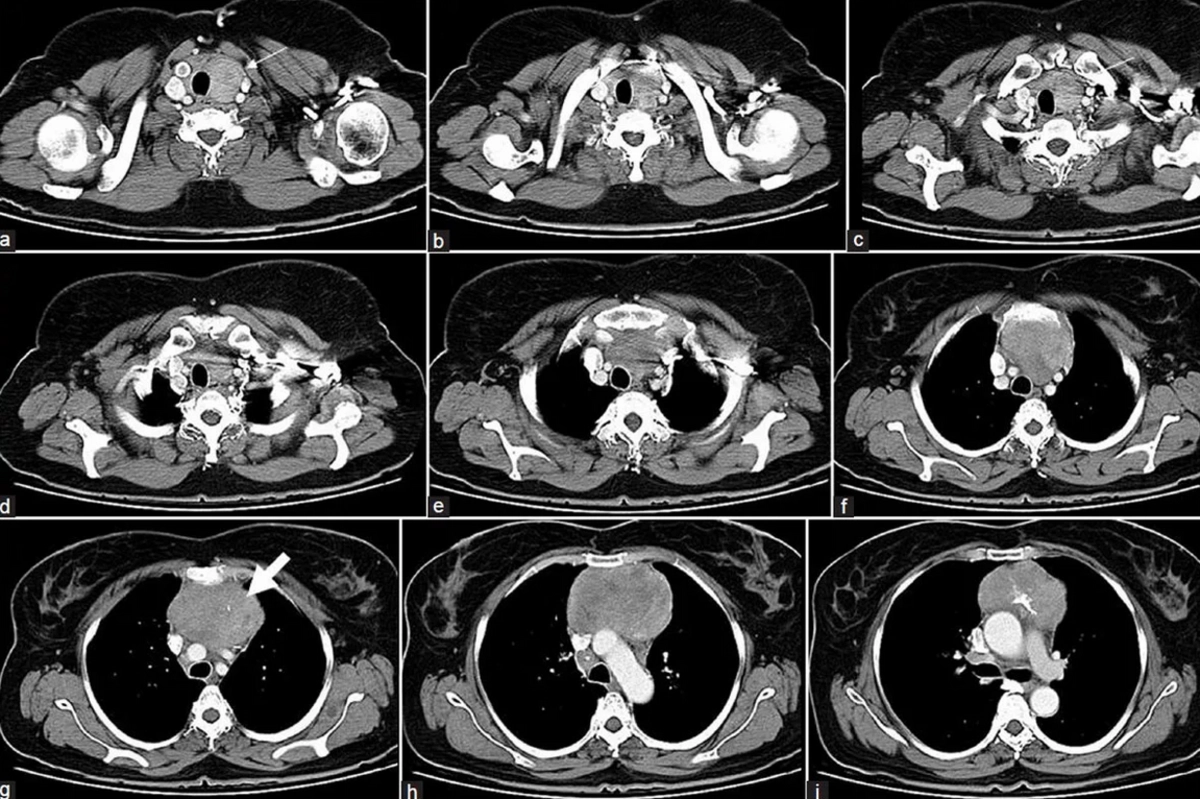

Международная команда исследователей опубликовала статью в Американском журнале рентгенологии, в которой говорится, что выявлена высокая частота отрицательных результатов КТ грудной клетки среди молодых пациентов с лабораторно подтвержденным COVID-19.

В исследовании ученые анализировали результаты КТ и клинические симптомы 30 детей (в возрасте от 10 месяцев до 18 лет), у которых подтвердился коронавирус.

Все пациенты после положительных анализов прошли исследования на КТ-визуализаторе, который оценивал степень поражения легких.

Результаты КТ у детей часто были отрицательными (77%). В остальных положительных случаях у пациентов наблюдались признаки гало, — говорится в исследовании.

Симптом обратного гало — проявления организующейся пневмонии: в грудной клетке происходит частичное заполнение альвеол, утолщение стенок ацинусов, по периферии — инфильтрация междолькового интерстиция.

В соответствии с общей симптоматикой у детей авторы этой статьи также наблюдали корреляцию между увеличением возраста и усилением тяжести результатов. В дальнейшем ученые, усомнившись в результативности КТ-диагностики при лечении COVID-19 у детей, подвергли 11 из 30 пациентов (37%) повторной КТ органов грудной клетки: в 10 случаях (91%) обследование не показало никаких изменений.